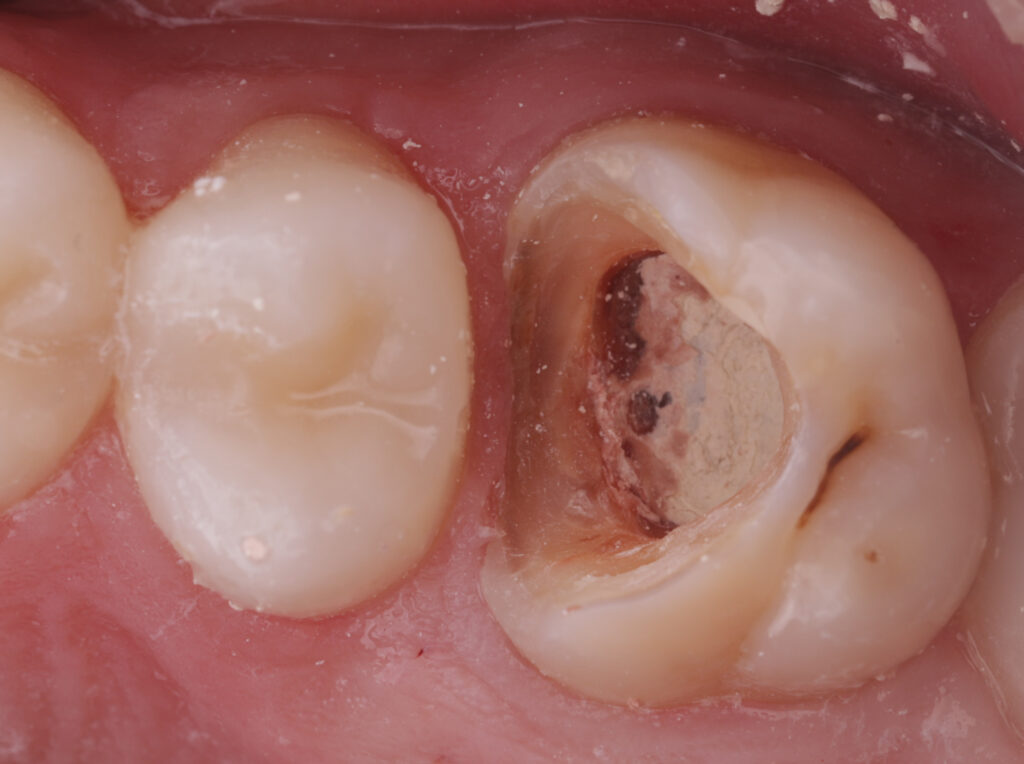

During the first visit, all carious tissues were removed, and the missing wall was restored using Asteria A3B material. The root canals were de-obturated, and a missed MB2 canal was identified. The canals were temporarily obturated with calcium hydroxide.

Two weeks later, the canals were irrigated with 5.25% sodium hypochlorite with ultrasonic activation (10 cycles), and permanent obturation of the root canals was performed using AH Plus sealer and gutta-percha.